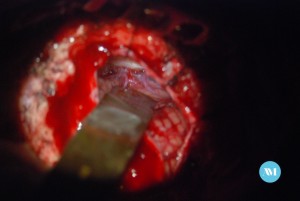

Algunos pacientes pueden requerir cirugía para aliviar la presión sobre el nervio. Las técnicas:

- Cirugía para extirpar un vaso sanguíneo que está ejerciendo presión sobre el nervio trigémino (llamada descompresión microvascular o DMV).